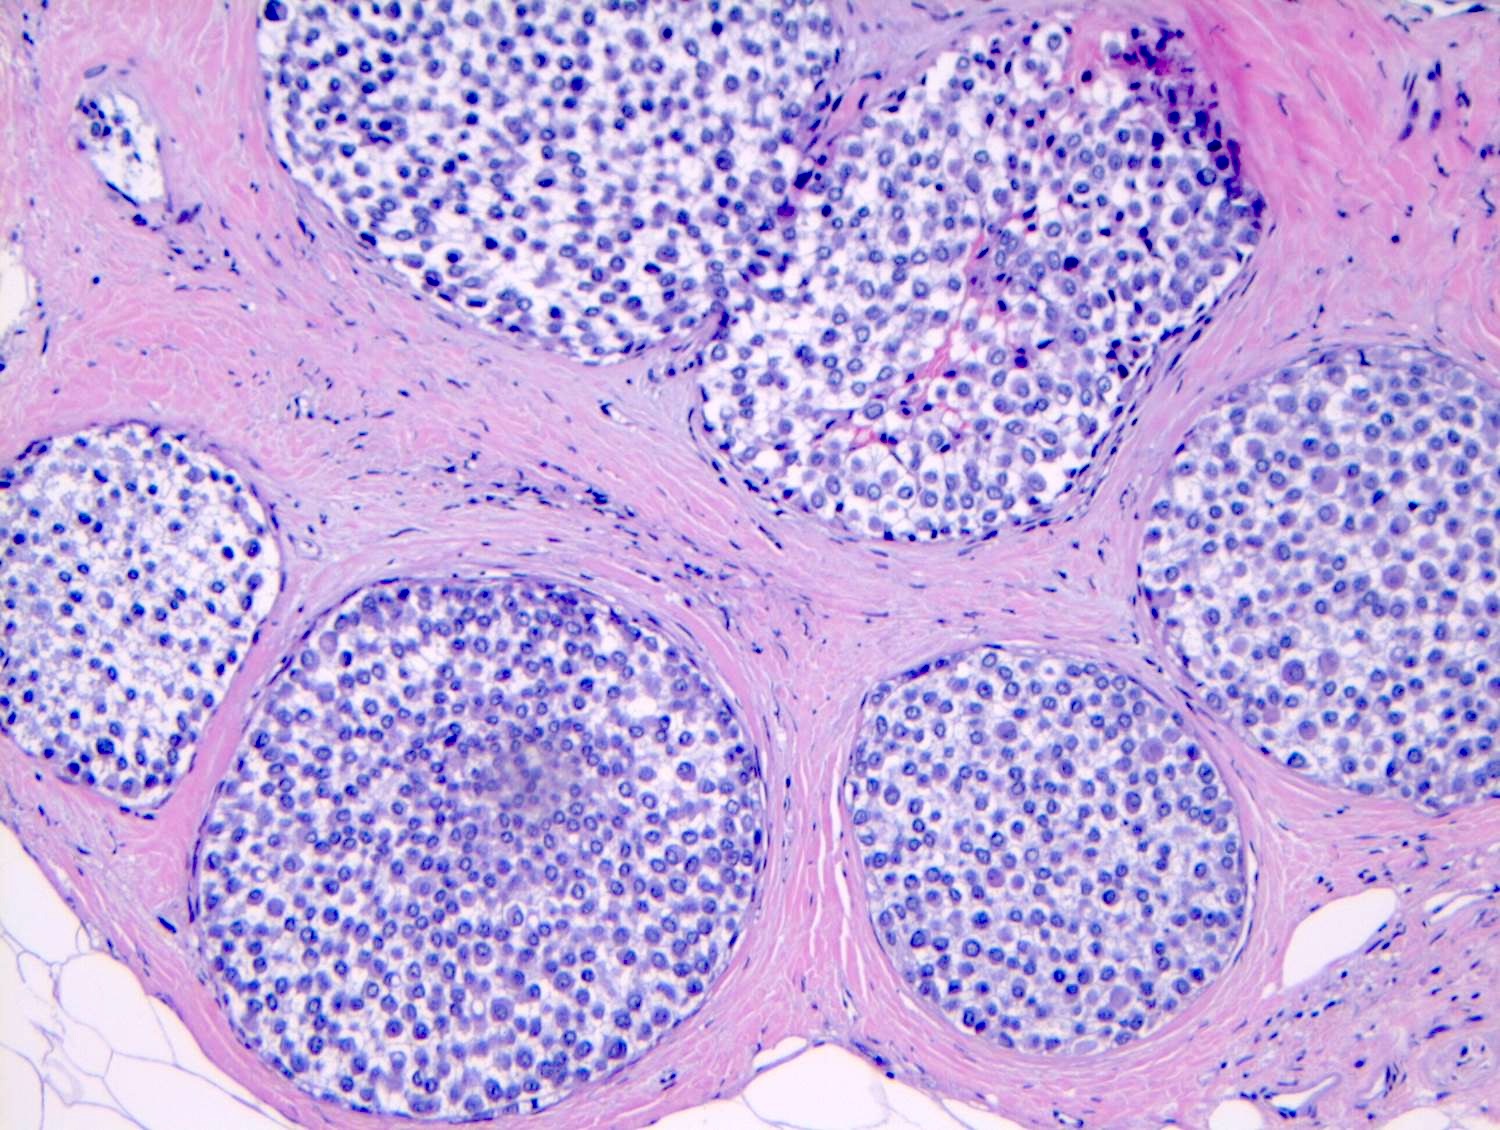

Microscopic (histologic) description

- LCIS involves the terminal duct lobular unit (TDLU), filling and distending acini

- > 50% of the acini in a TDLU must be filled and expanded to qualify as LCIS; otherwise, called atypical lobular neoplasia

- Lobular distention is defined as the presence of ≥ 8 cells in the cross sectional diameter of an acinus

- Involved lobules may be compared with uninvolved lobules to estimate the degree of distension

- ALH only partially involves the lobule by filling up the acini without significant distention

- Classic LCIS cells are monomorphic, evenly spaced, loosely cohesive and do not show polarization or gland formation

- Cytoplasm of LCIS cells is typically pale to lightly eosinophilic with indistinct cell borders

- Outer layer of myoepithelial cells is retained in the acini and ducts involved but it may be attenuated

Microscopic (histologic) images

Contributed by Anna Biernacka, M.D., Ph.D.